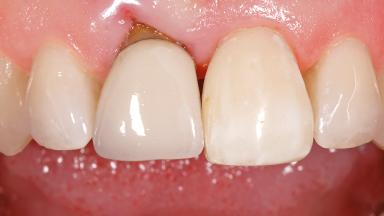

Early Placement of an Implant in a Maxillary Right Central Incisor Site

This 41-year-old female patient was referred to the clinic for the replacement of the right central incisor, since the tooth had developed a root fracture in the long axis that made extraction necessary. The healthy, non-smoking patient was first seen with the tooth still in place. A detailed Esthetic Risk Assessment was performed.The patient was worried about her dental esthetics and had high expectations for a successful treatment outcome from an esthetic point of view. The patient had a medium lip line that displayed parts of the gingiva in the anterior maxilla upon smile.

Soft Tissue Contour and Volume Slightly compromised